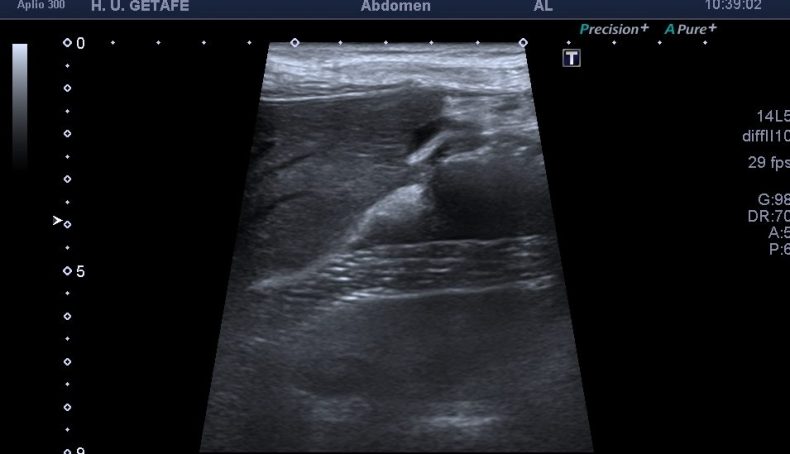

Con la sonda de alta frecuencia y en determinados pacientes puede ver esta estructura metálica de una manera más definida con más detalle.

Observa y controla siempre la anatomía de la zona.